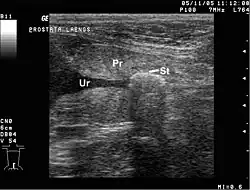

Für die Diagnostik und Kontrolle ist die Ultraschalluntersuchung die erste Wahl, sowohl in Notfall- als auch in Routinesituationen. Konventionelles Röntgen kann bei schattengebenden Konkrementen angewendet werden, z. B. bei Steinen aus Calciumsalzen.[10]